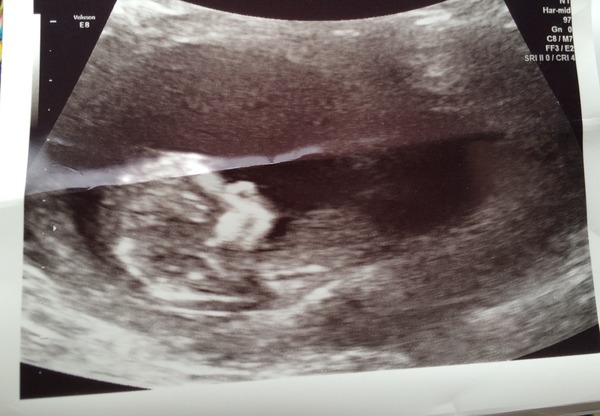

I am 13+3 with my 3rd baby. My eldest son is almost 3 and is fine. My second was lost to a late missed miscarriage (he died around 18 weeks, discovered at the 20 week scan). We had a post mortem but there was no reason found, he was essentially a healthy baby, and we were just told that it was one of those things. My nuchal fold / combined blood test tesults have come back as a 1:47 risk factor. I don't know my precise figures but she said NT was slightly high (but it can't have been dramatic as nothing was mentioned at the scan), hCG was normal and PAPP-A was low. She thought it was the PAPP-A that was the reason the risk factor was high, as well as my age (I'm